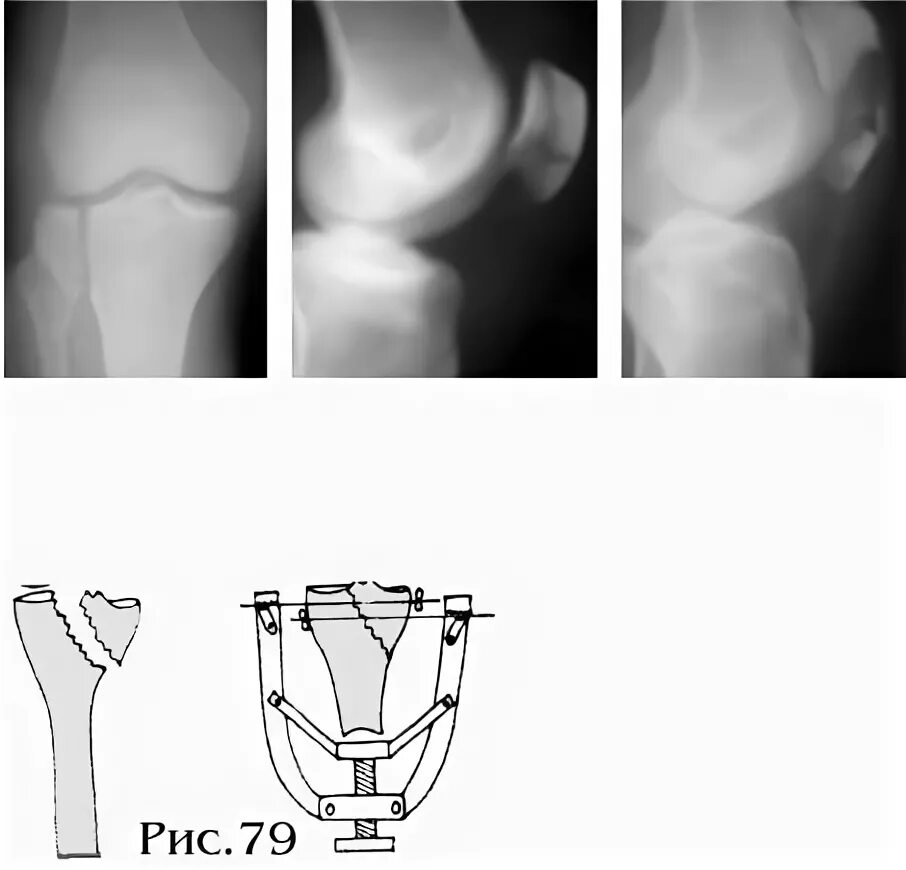

Перелом без смещения форум